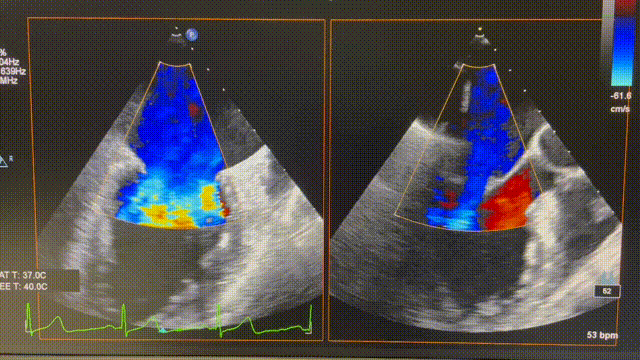

患者为74岁女性。术前心超显示后叶P2脱垂,伴极重度二尖瓣反流(VCW 9mm*16mm),图2。患者全麻后,在超声和射线引导下器械经股静脉穿刺房间隔,通过输送系统送入患者左心房,到达二尖瓣膜反流处,在经食道超声及DSA引导下,术者通过反复评估二尖瓣膜脱垂范围、抓捕位置、反流程度,精准夹合,成功植入1枚ValveClasp瓣膜夹。术后即刻左房压力及V波减低,患者反流从5+减少到1+(图3),跨二尖瓣平均压差3mmHg,肺静脉逆流消失,血流动力学改善明显,手术取得圆满成功。

图3 术后心超图。